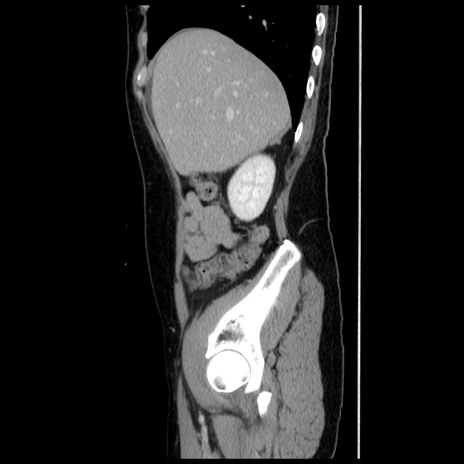

冠状断像

【症例】 50歳代女性

【主訴】 腹痛

【現病歴】前日生レバーを食べた。今朝に排便あり。 昼前に突然発症の腹痛を生じ、当院救急外来を受診した。

【既往歴】 子宮筋腫にてで子宮全摘後

【身体所見】 意識清明、腹部:平坦、軟、下腹部やや左を中心に圧痛・反跳痛あり、筋性防御あり

【データ】WBC 7800、CRP 0.07